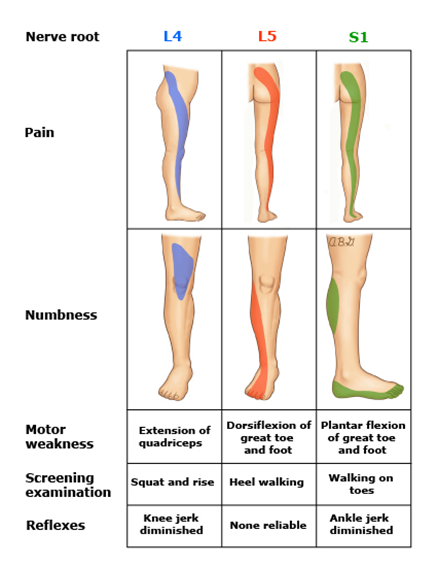

위에서 언급한 바와 같이, 요추 추간판탈출증의 탈출 부위에 따라서도 증상이 조금씩 다릅니다.

1) 요추 4 ~ 5번(L4-5)

- 압박되는 신경: 요추 5번(L5)

- 엉덩이에서 다리 뒤쪽으로 감각이 무뎌지며, 저리거나 당기는 통증이 발등과 엄지발까락까지 발생

2) 요추 5번 ~ 천추 1번(L5-S1)

- 압박되는 신경: 천추 1번(S1)

- 엉덩이 부위에서 다리 뒤쪽 중앙과 종아리 쪽으로 감각기 무뎌지며, 저리거나 당기는 통증이 발바닥과 새끼발가락까지 발생